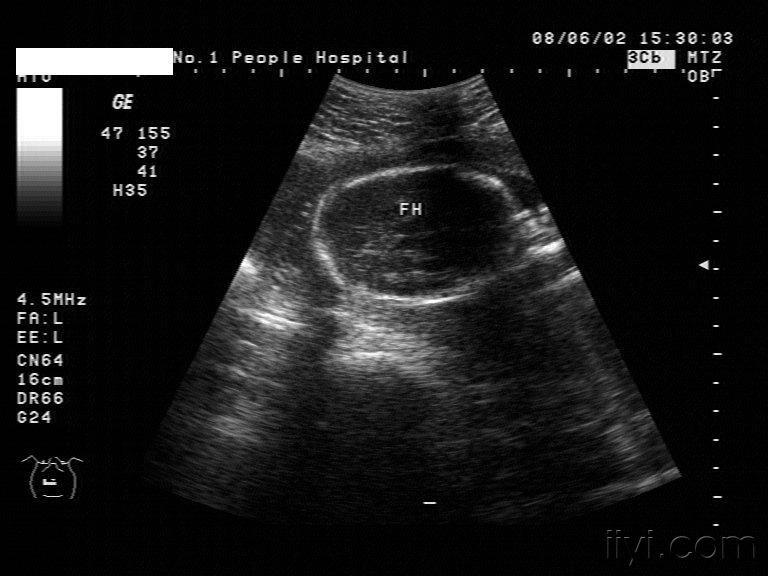

柠檬头,常常合并香蕉小脑,脑积水和开放性脊柱裂.

见过这种柠檬形的胎头吗

图片尺寸768x576